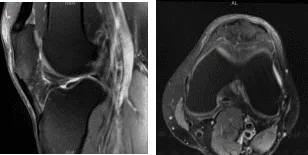

The patient presented MRI results that showed mild to moderate insertional quadriceps and proximal patellar tendinosis. There is prominent spurring along the inferior pole of the patella without a separate ossific fragment or surrounding bone marrow edema indicative of previous traction injury.

No meniscal tear or ligament injury. Cartilage is preserved. For the right knee, the X Ray results have shown Shallow undersurface tear at the posterior horn/body junction of the medial meniscus and undersurface fraying of the posterior horn.

Mild quadriceps and patellar tendinosis without a tear. Mild prepatellar bursitis and moderate surrounding soft tissue edema. We discussed treatment with the patient. The patient had tried physical therapy in the past.

MRI-3T Left Knee non-contrast

MRI-3t Right Knee non-contrast